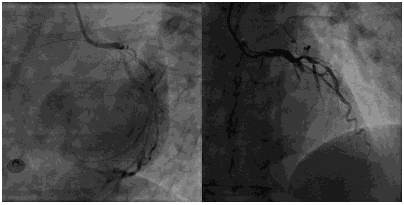

手术过程:BMW导丝通过LAD近中段闭塞病变处至远端,送入抽吸导管,抽吸血栓后可见全程显影,注入替罗非班,用PWR球囊2.0×15 mm用8-12 atm×10 s×2次扩张,用Voyager球囊2.0×15 mm用8-12 atm×10 s×2次扩张,选Execel支架2.5×36 mm植入LAD中段病变用12 atm×10 s×1次扩张,再用NC 球囊2.75×15 mm×12-22 atm×10 s×4次扩张,用Grip球囊3.0 mm×12 mm用12 atm×10 s×4次扩张。造影示未见残余狭窄,TIMI血流3级。

![]()

术后心电图: